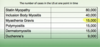

FYI: see chart